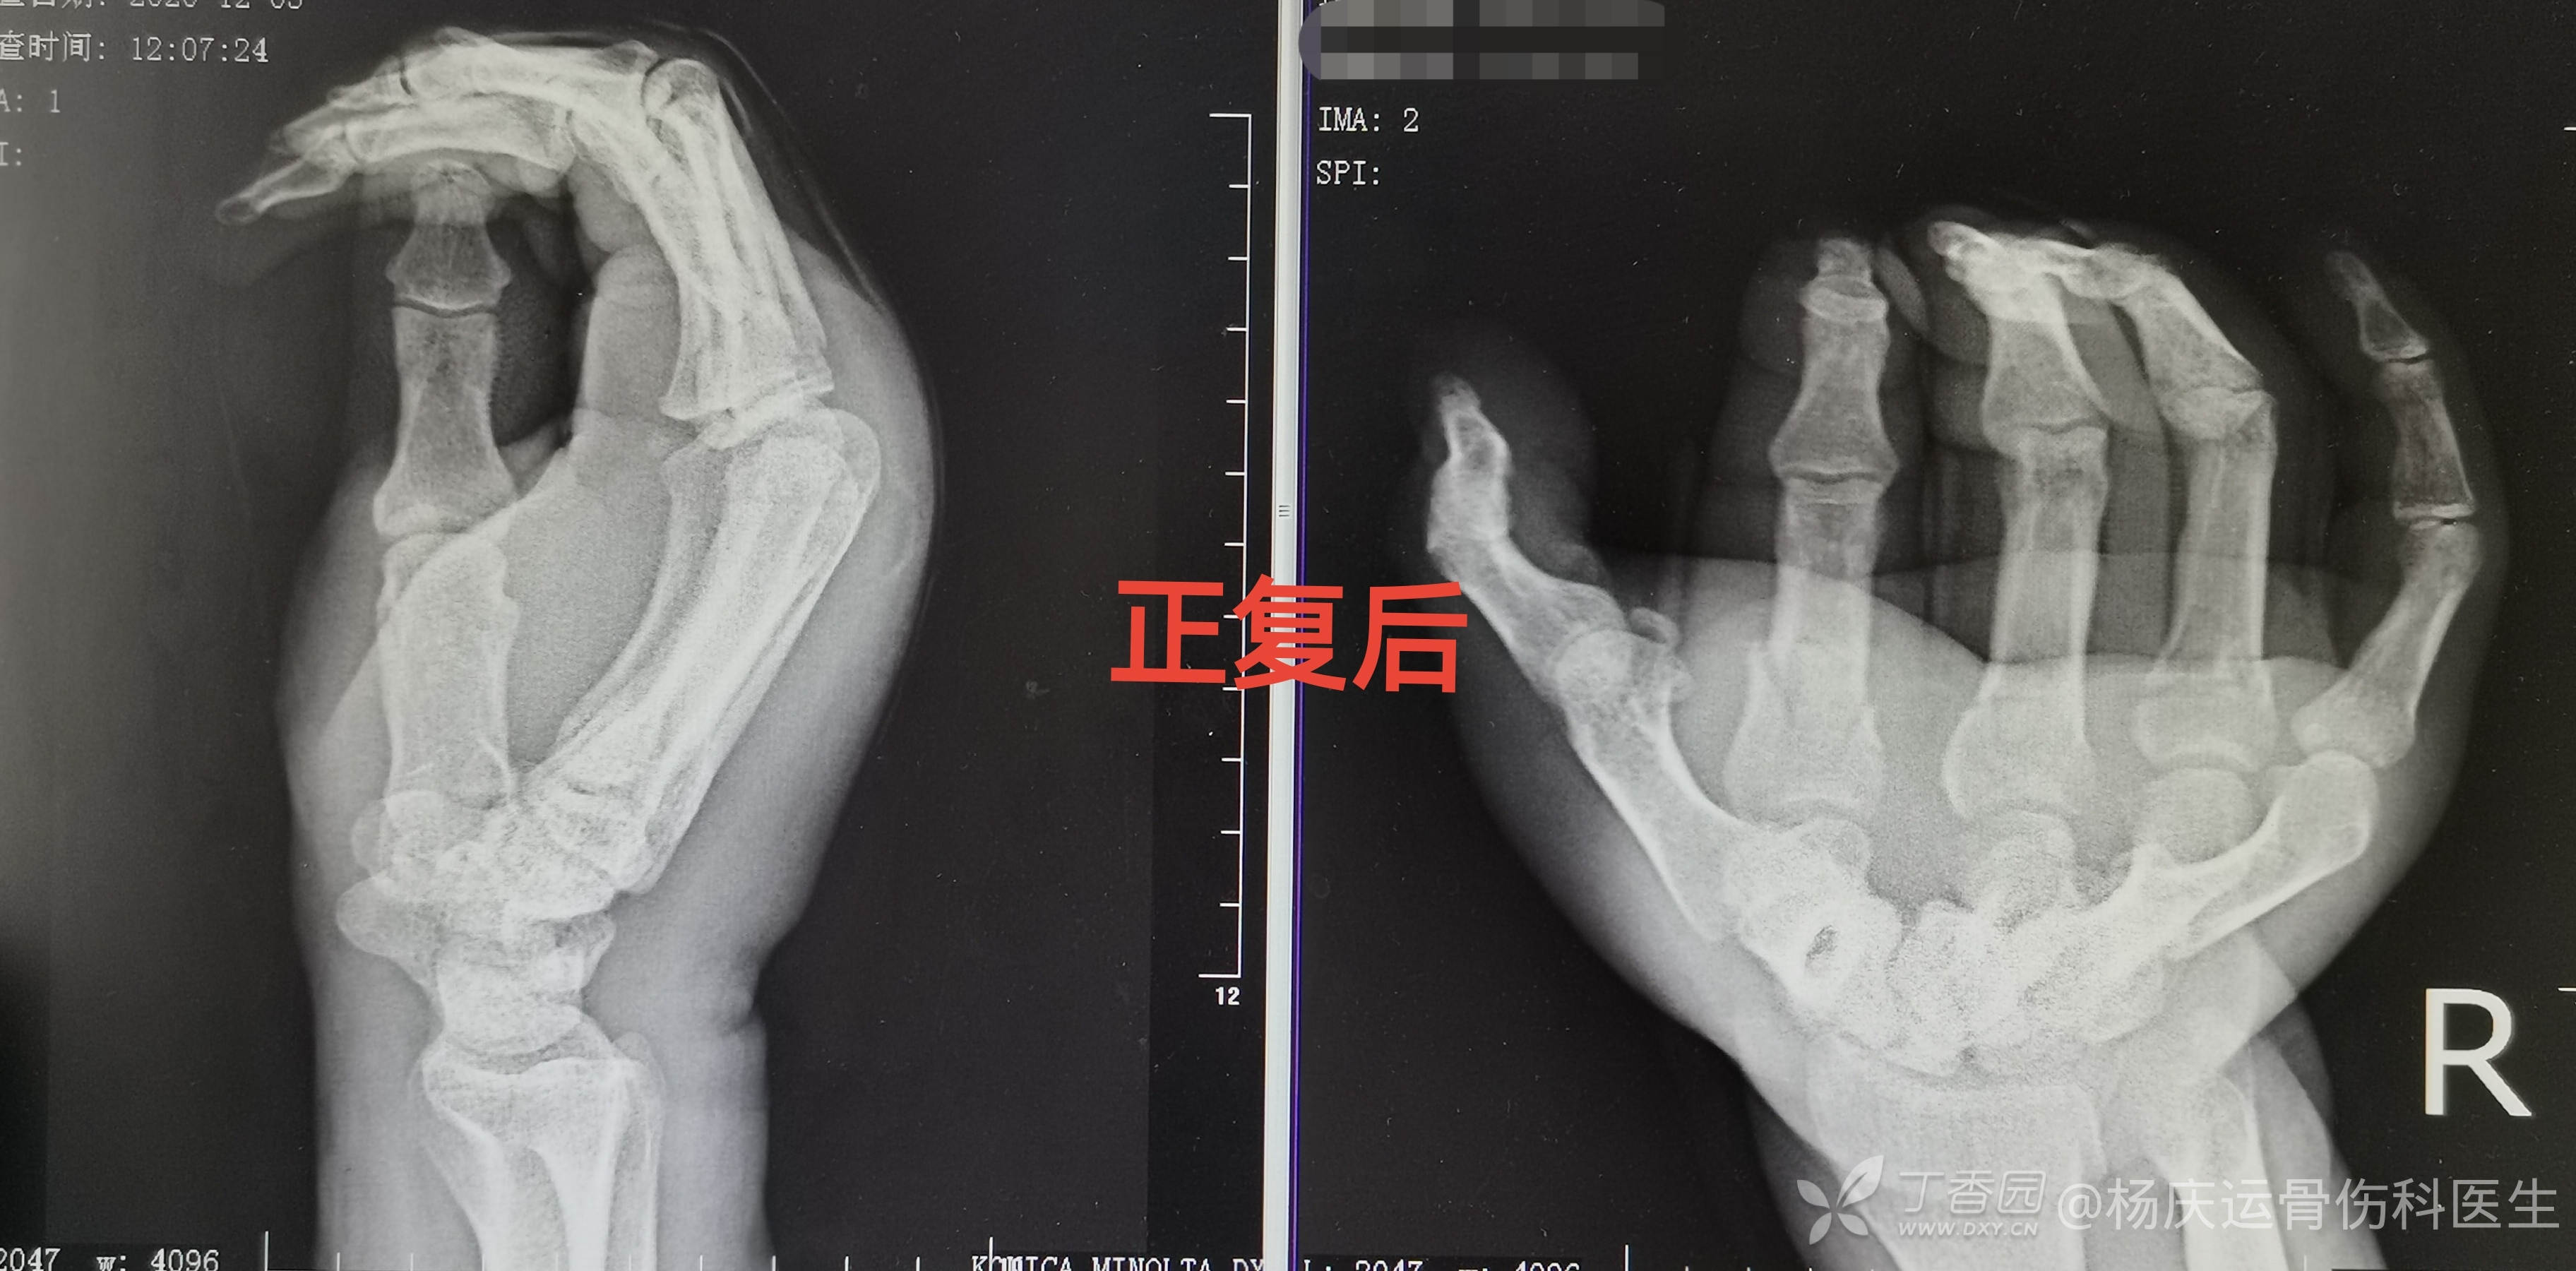

正复后